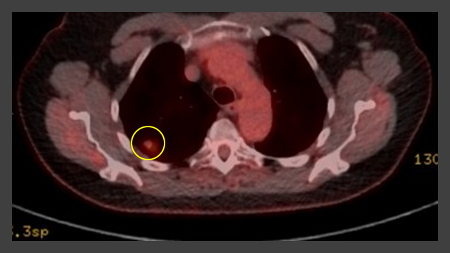

The Herder model (that incorporates F-18 fluorodeoxyglucose [FDG] avidity) has been found to be more accurate in patients who undergo positron emission tomography (PET-CT) evaluation of pulmonary nodule.[38][39] UK guidelines recommend that selected patients (pre-test probability of malignancy >10% and solid component of a nodule greater than the local threshold size [usually 8 to 10 mm]) are evaluated by PET-CT and that the Herder model is used to determine risk thereafter.[4][40]

PET scanning can have a role in staging of tumours and has an especially high negative predictive value in excluding mediastinal involvement.[43][Figure caption and citation for the preceding image starts]: Computed tomography (CT) sections from two cases with benign perifissural nodules. Note the smooth margins and the normal undisturbed adjacent fissureFrom the collection of Dr George Tsaknis, MD, PhD, FRCP(London), MRQA, MAcadMEd, PGCert; used with permission [Citation ends].

[Figure caption and citation for the preceding image starts]: PET CT scan with 18-fluorodeoxyglucose (18-FDG) showing a high uptake peripheral left lung lesion. Surgical resection confirmed a moderately differentiated squamous cell lung cancerFrom the collection of Dr George Tsaknis, MD, PhD, FRCP(London), MRQA, MAcadMEd, PGCert; used with permission [Citation ends].